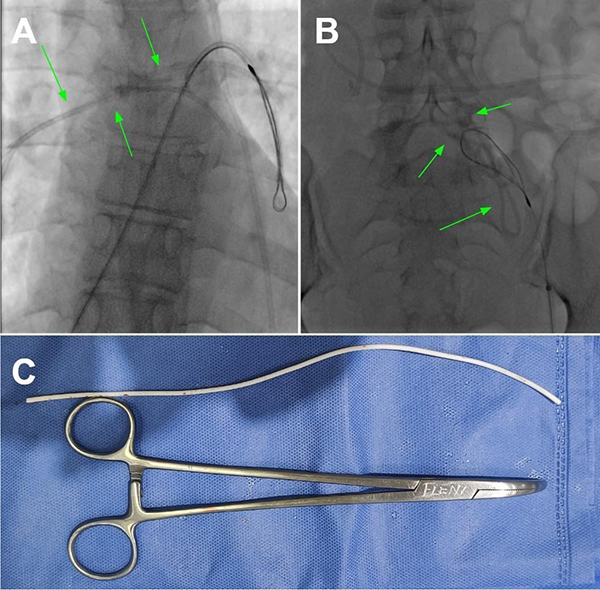

Tras 2 meses, la paciente volvió a consultar en guardia por náuseas, cefalea bifrontal con irradiación holocraneana de intensidad moderada y vómitos. Al examen físico se constató limitación de la mirada superior y colección líquida sobre herida craneal de derivación. Se realizó TC de cerebro con evidencia de ventriculomegalia y desconexión de catéter distal a la válvula (Figura 1). El estudio radiográfico reveló migración caudal del segmento distal del catéter al corazón (Figura 2). El segmento migrado fue rescatado mediante un abordaje endovascular transfemoral, en el cual se enroscó el catéter migrado con un catéter pigtail y se lo desplazó hasta la vena ilíaca primitiva izquierda para luego ser capturado a nivel ilíaco con un lazo trilobulado (Figura 3).

Figura 2. A y B. Radiografías de frente y perfil respectivamente realizadas previo a la intervención endovascular en donde se evidencia migración del catéter distal a la cavidad cardíaca (flechas verdes).

Figura 3. A. y B. Imágenes radioscópicas del procedimiento endovascular efectuado en el cuál se recupera y exterioriza el catéter distal migrado. C. Fotografía del catéter una vez retirado.